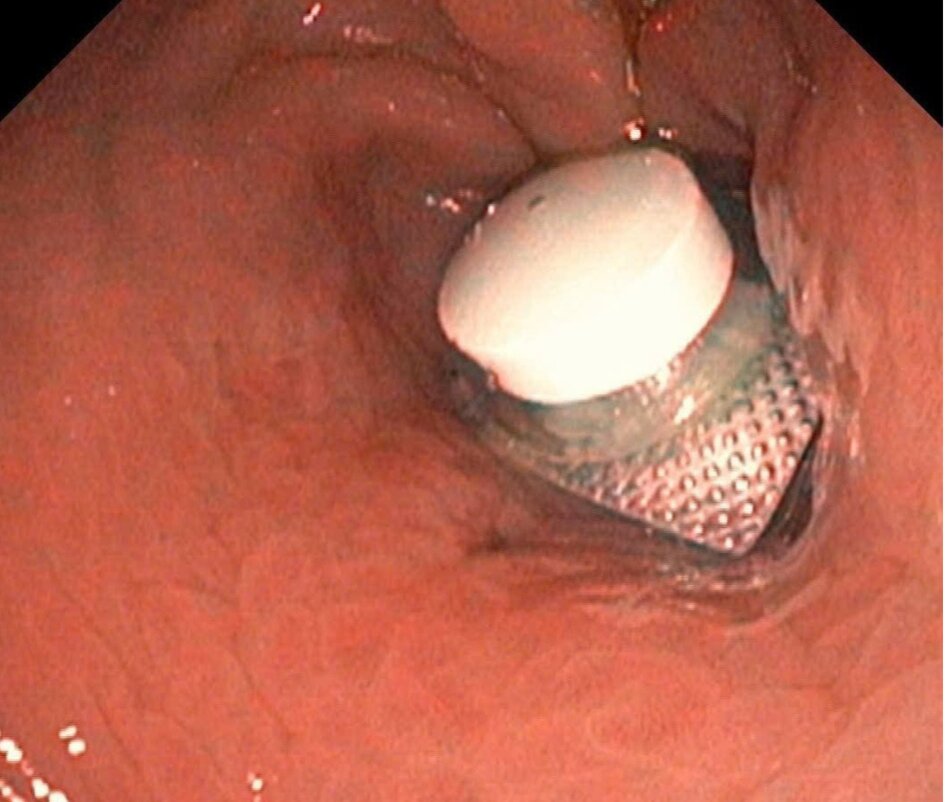

Viên thuốc còn nguyên vỏ được phát hiện tại vị trí cuối dạ dày của bệnh nhân. Ảnh: Bệnh viện cung cấp

Trước đó, bệnh nhân nam 52 tuổi nhập viện cấp cứu trong tình trạng đau bụng dữ dội. Qua thăm khám lâm sàng, bệnh nhân được bác sĩ chỉ định nội soi dạ dày và phát hiện tại môn vị có dị vật là viên thuốc còn nguyên vỏ, gây trầy xước niêm mạc dạ dày.

Ngay sau đó, các bác sĩ đã tiến hành nội soi gắp dị vật và lấy ra thành công, đảm bảo an toàn cho người bệnh.